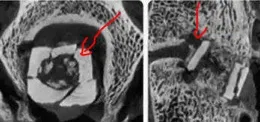

金属植入物在日后的影像学检查中或多或少会存在CT或X光的金属伪影,从而影响日后疾病的诊断。PEEK材料在X光和CT中由于原子核结构问题,就从原理上避免这种现象。

图为:GE开发的减低金属伪影的技术

可以看到金属伪影会干扰实际临床判断。虽然有降噪技术但和原生无伪影的PEEK材料相比还是多了很多麻烦和时间成本。PEEK植入体影像数据,基本无干扰。